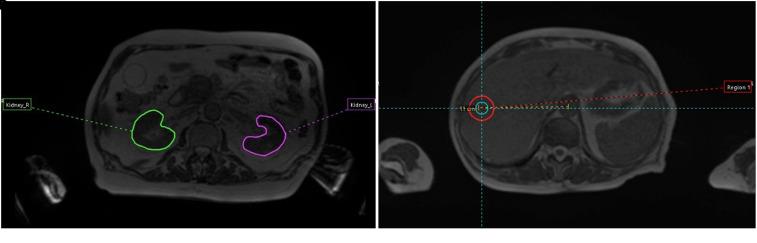

Radiomics entails the extraction of quantitative imaging biomarkers (or radiomics features) hypothesized to provide additional pathophysiological and/or clinical information compared to qualitative visual observation and interpretation. This retrospective study explores the variability of radiomics features extracted from images acquired with the 0.35 T scanner of an integrated MRI-Linac. We hypothesized we would be able to identify features with high repeatability and reproducibility over various imaging conditions using phantom and patient imaging studies. We also compared findings from the literature relevant to our results. Eleven scans of a Magphan RT phantom over 13 months and 11 scans of a ViewRay Daily QA phantom over 11 days constituted the phantom data. Patient datasets included 50 images from ten anonymized stereotactic body radiation therapy (SBRT) pancreatic cancer patients (50 Gy in 5 fractions). A True Fast Imaging with Steady-State Free Precession (TRUFI) pulse sequence was selected, using a voxel resolution of 1.5 mm × 1.5 mm × 1.5 mm and 1.5 mm × 1.5 mm × 3.0 mm for phantom and patient data, respectively. A total of 1087 shape-based, first, second, and higher order features were extracted followed by robustness analysis. Robustness was assessed with the Coefficient of Variation (CoV < 5%). We identified 130 robust features across the datasets. Robust features were found within each category, except for 2 second-order sub-groups, namely, Gray Level Size Zone Matrix (GLSZM) and Neighborhood Gray Tone Difference Matrix (NGTDM). Additionally, several robust features agreed with findings from other stability assessments or predictive performance studies in the literature. We verified the stability of the 0.35 T scanner of an integrated MRI-Linac for longitudinal radiomics phantom studies and identified robust features over various imaging conditions. We conclude that phantom measurements can be used to identify robust radiomics features. More stability assessment research is warranted.

放射组学需要提取定量成像生物标志物(或放射组学特征),与定性视觉观察和解释相比,这些特征假设可以提供额外的病理生理和/或临床信息。这项回顾性研究探索了从集成 MRI-直线加速器的 0.35T 扫描仪获得的图像中提取的放射组学特征的可变性。我们假设能够在各种成像条件下使用体模和患者成像研究来识别具有高可重复性和可再现性的特征。我们还比较了与我们的结果相关的文献中的发现。 11 个 Magphan RT 体模在 13 个月内和 11 个 ViewRay Daily QA 体模在 11 天内进行的扫描构成了体模数据。患者数据集包括来自十个匿名立体定向体部放射治疗(SBRT)胰腺癌患者的 50 个图像(50Gy 分 5 次)。选择了 True Fast Imaging with Steady-State Free Precession(TRUFI)脉冲序列,体模数据的体素分辨率为 1.5mm×1.5mm×1.5mm,患者数据的体素分辨率为 1.5mm×1.5mm×3.0mm。提取了总共 1087 个基于形状的、一阶、二阶和更高阶特征,然后进行稳健性分析。稳健性用变异系数(CoV<5%)评估。 我们在数据集之间识别了 130 个稳健的特征。除了两个二阶子组,即灰度大小区域矩阵(GLSZM)和邻域灰度差矩阵(NGTDM)外,每个类别都找到了稳健的特征。此外,一些稳健的特征与文献中其他稳定性评估或预测性能研究的发现一致。 我们验证了集成 MRI-直线加速器的 0.35T 扫描仪在纵向放射组学体模研究中的稳定性,并在各种成像条件下识别了稳健的特征。我们得出结论,体模测量可用于识别稳健的放射组学特征。需要进行更多的稳定性评估研究。